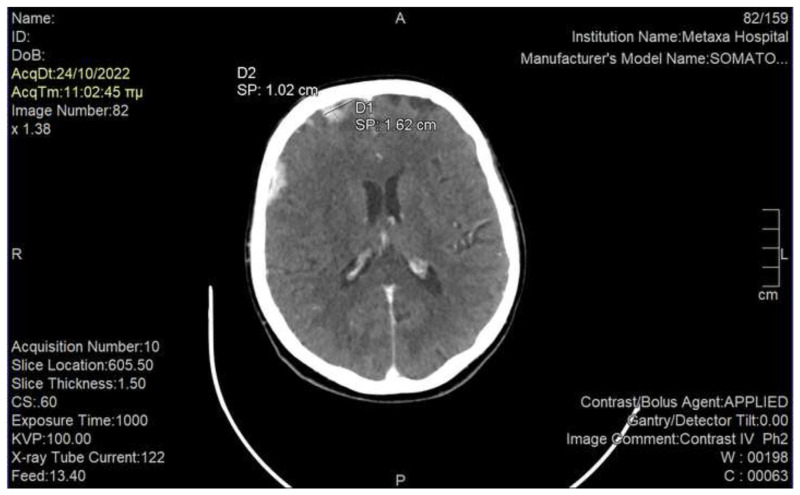

Phantosmia belongs to the group of olfactory dysfunctions. It is more commonly described in psychiatric conditions and some cases of viral infections, but it has been also rarely described in cancer patients who develop primary or metastatic central nervous system tumors; the early identification of this symptom in this population is crucial, as it could lead to timely diagnosis and treatment through a multidisciplinary approach. With the current report we present the case of a 60-year-old lady with metastatic breast cancer and without known preexisting brain metastases, who developed acute phantosmia without other neurological deficits; computed tomography of the brain revealed multiple brain metastases, which were attributed to the malignancy, and for which she was effectively treated with whole brain irradiation and antipsychotic as well as anticonvulsant medications. Furthermore, we underline the value of cooperation between the various specialties that could aid in diagnosis and management of this symptomatology. Phantosmia is an extremely rare symptom in cancer patients, and its appearance should alarm physicians to rapidly investigate a possible progression of disease in the central nervous system. Multidisciplinary approach is needed for the optimal management of these patients.